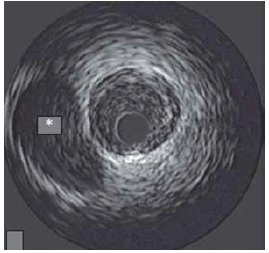

Ao realizar ultrassonografia intravascular da artéria circunflexa para avaliação de placa e angioplastia, observa-se a imagem marcada com o asterisco.

(Arquivo pessoal; imagem usada com autorização)

A imagem indica